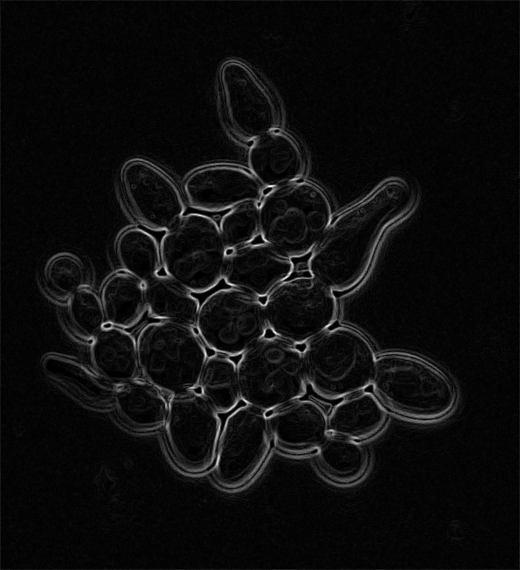

Raw Data 𝒟={(xi,yi)}i=1N\mathcal{D}=\{(x_{i},y_{i})\}_{i=1}^{N}caligraphic_D = { ( italic_x start_POSTSUBSCRIPT italic_i end_POSTSUBSCRIPT , italic_y start_POSTSUBSCRIPT italic_i end_POSTSUBSCRIPT ) } start_POSTSUBSCRIPT italic_i = 1 end_POSTSUBSCRIPT start_POSTSUPERSCRIPT italic_N end_POSTSUPERSCRIPT Refer to captionRefer to captionRefer to captionRefer to captionRefer to captionRefer to captionRefer to caption Edge-enhanced E(xi)E(x_{i})italic_E ( italic_x start_POSTSUBSCRIPT italic_i end_POSTSUBSCRIPT ) Refer to caption Refer to caption Refer to caption Refer to caption Refer to caption Refer to caption Refer to caption Extract ϕ(xi)\phi(x_{i})italic_ϕ ( italic_x start_POSTSUBSCRIPT italic_i end_POSTSUBSCRIPT )Train fθf_{\theta}italic_f start_POSTSUBSCRIPT italic_θ end_POSTSUBSCRIPTon {(xi,yi)}i=1N\{(x_{i},y_{i})\}^{N}_{i=1}{ ( italic_x start_POSTSUBSCRIPT italic_i end_POSTSUBSCRIPT , italic_y start_POSTSUBSCRIPT italic_i end_POSTSUBSCRIPT ) } start_POSTSUPERSCRIPT italic_N end_POSTSUPERSCRIPT start_POSTSUBSCRIPT italic_i = 1 end_POSTSUBSCRIPTTrain fθf^{\star}_{\theta}italic_f start_POSTSUPERSCRIPT ⋆ end_POSTSUPERSCRIPT start_POSTSUBSCRIPT italic_θ end_POSTSUBSCRIPTon {(E(xi),yi)}i=1N\{(E(x_{i}),y_{i})\}^{N}_{i=1}{ ( italic_E ( italic_x start_POSTSUBSCRIPT italic_i end_POSTSUBSCRIPT ) , italic_y start_POSTSUBSCRIPT italic_i end_POSTSUBSCRIPT ) } start_POSTSUPERSCRIPT italic_N end_POSTSUPERSCRIPT start_POSTSUBSCRIPT italic_i = 1 end_POSTSUBSCRIPTFine-tune fθf_{\theta}italic_f start_POSTSUBSCRIPT italic_θ end_POSTSUBSCRIPT on modality data 𝒟mod\mathcal{D}^{mod}caligraphic_D start_POSTSUPERSCRIPT italic_m italic_o italic_d end_POSTSUPERSCRIPTFine-tune fθf^{\star}_{\theta}italic_f start_POSTSUPERSCRIPT ⋆ end_POSTSUPERSCRIPT start_POSTSUBSCRIPT italic_θ end_POSTSUBSCRIPT on modality data 𝒟mod\mathcal{D}^{mod}caligraphic_D start_POSTSUPERSCRIPT italic_m italic_o italic_d end_POSTSUPERSCRIPTCompare perf. δi=𝕀[fθ>fθ]\delta_{i}=\mathbb{I}[f^{\star}_{\theta}>f_{\theta}]italic_δ start_POSTSUBSCRIPT italic_i end_POSTSUBSCRIPT = blackboard_I [ italic_f start_POSTSUPERSCRIPT ⋆ end_POSTSUPERSCRIPT start_POSTSUBSCRIPT italic_θ end_POSTSUBSCRIPT > italic_f start_POSTSUBSCRIPT italic_θ end_POSTSUBSCRIPT ]Map meta-classifier m(ϕ(xi))δim(\phi(x_{i}))\rightarrow{}\delta_{i}italic_m ( italic_ϕ ( italic_x start_POSTSUBSCRIPT italic_i end_POSTSUBSCRIPT ) ) → italic_δ start_POSTSUBSCRIPT italic_i end_POSTSUBSCRIPTGeneral pre-training Modality-specific fine-tuning

(a) Training: Our approach to pre-training, modality-specific fine-tuning, and meta-classifier mapping.

Figure 1: Our approach: (a) training pipeline and (b) inference pipeline.